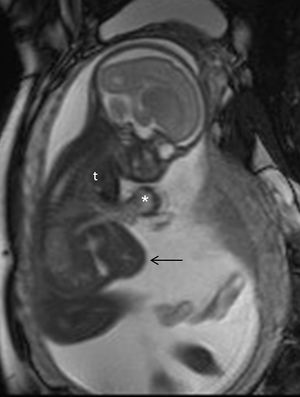

تصوير بالرنين المغناطيسي

التصوير بالرنين المغناطيسي، بدون وسط تباين في التصوير بالرنين المغناطيسي، لا يرتبط بأي خطر على الأم أو الجنين، وإلى جانب تخطيط الصدى الطبي هو الأسلوب المفضل للتصوير الطبي في الحمل.[1]

يستخدم التصوير بالرنين المغناطيسي عادة في النساء الحوامل المصابات بالألم البطني و / أو الألم الحوضي، أو في الاضطرابات العصبية المشتبه فيها، وأمراض المشيمة، والأورام، والعدوى، و / أو الأمراض القلبية الوعائية.[3] تعطي معايير الاستخدام المناسبة من قبل الكلية الأمريكية للأشعة تصنيف ≥7